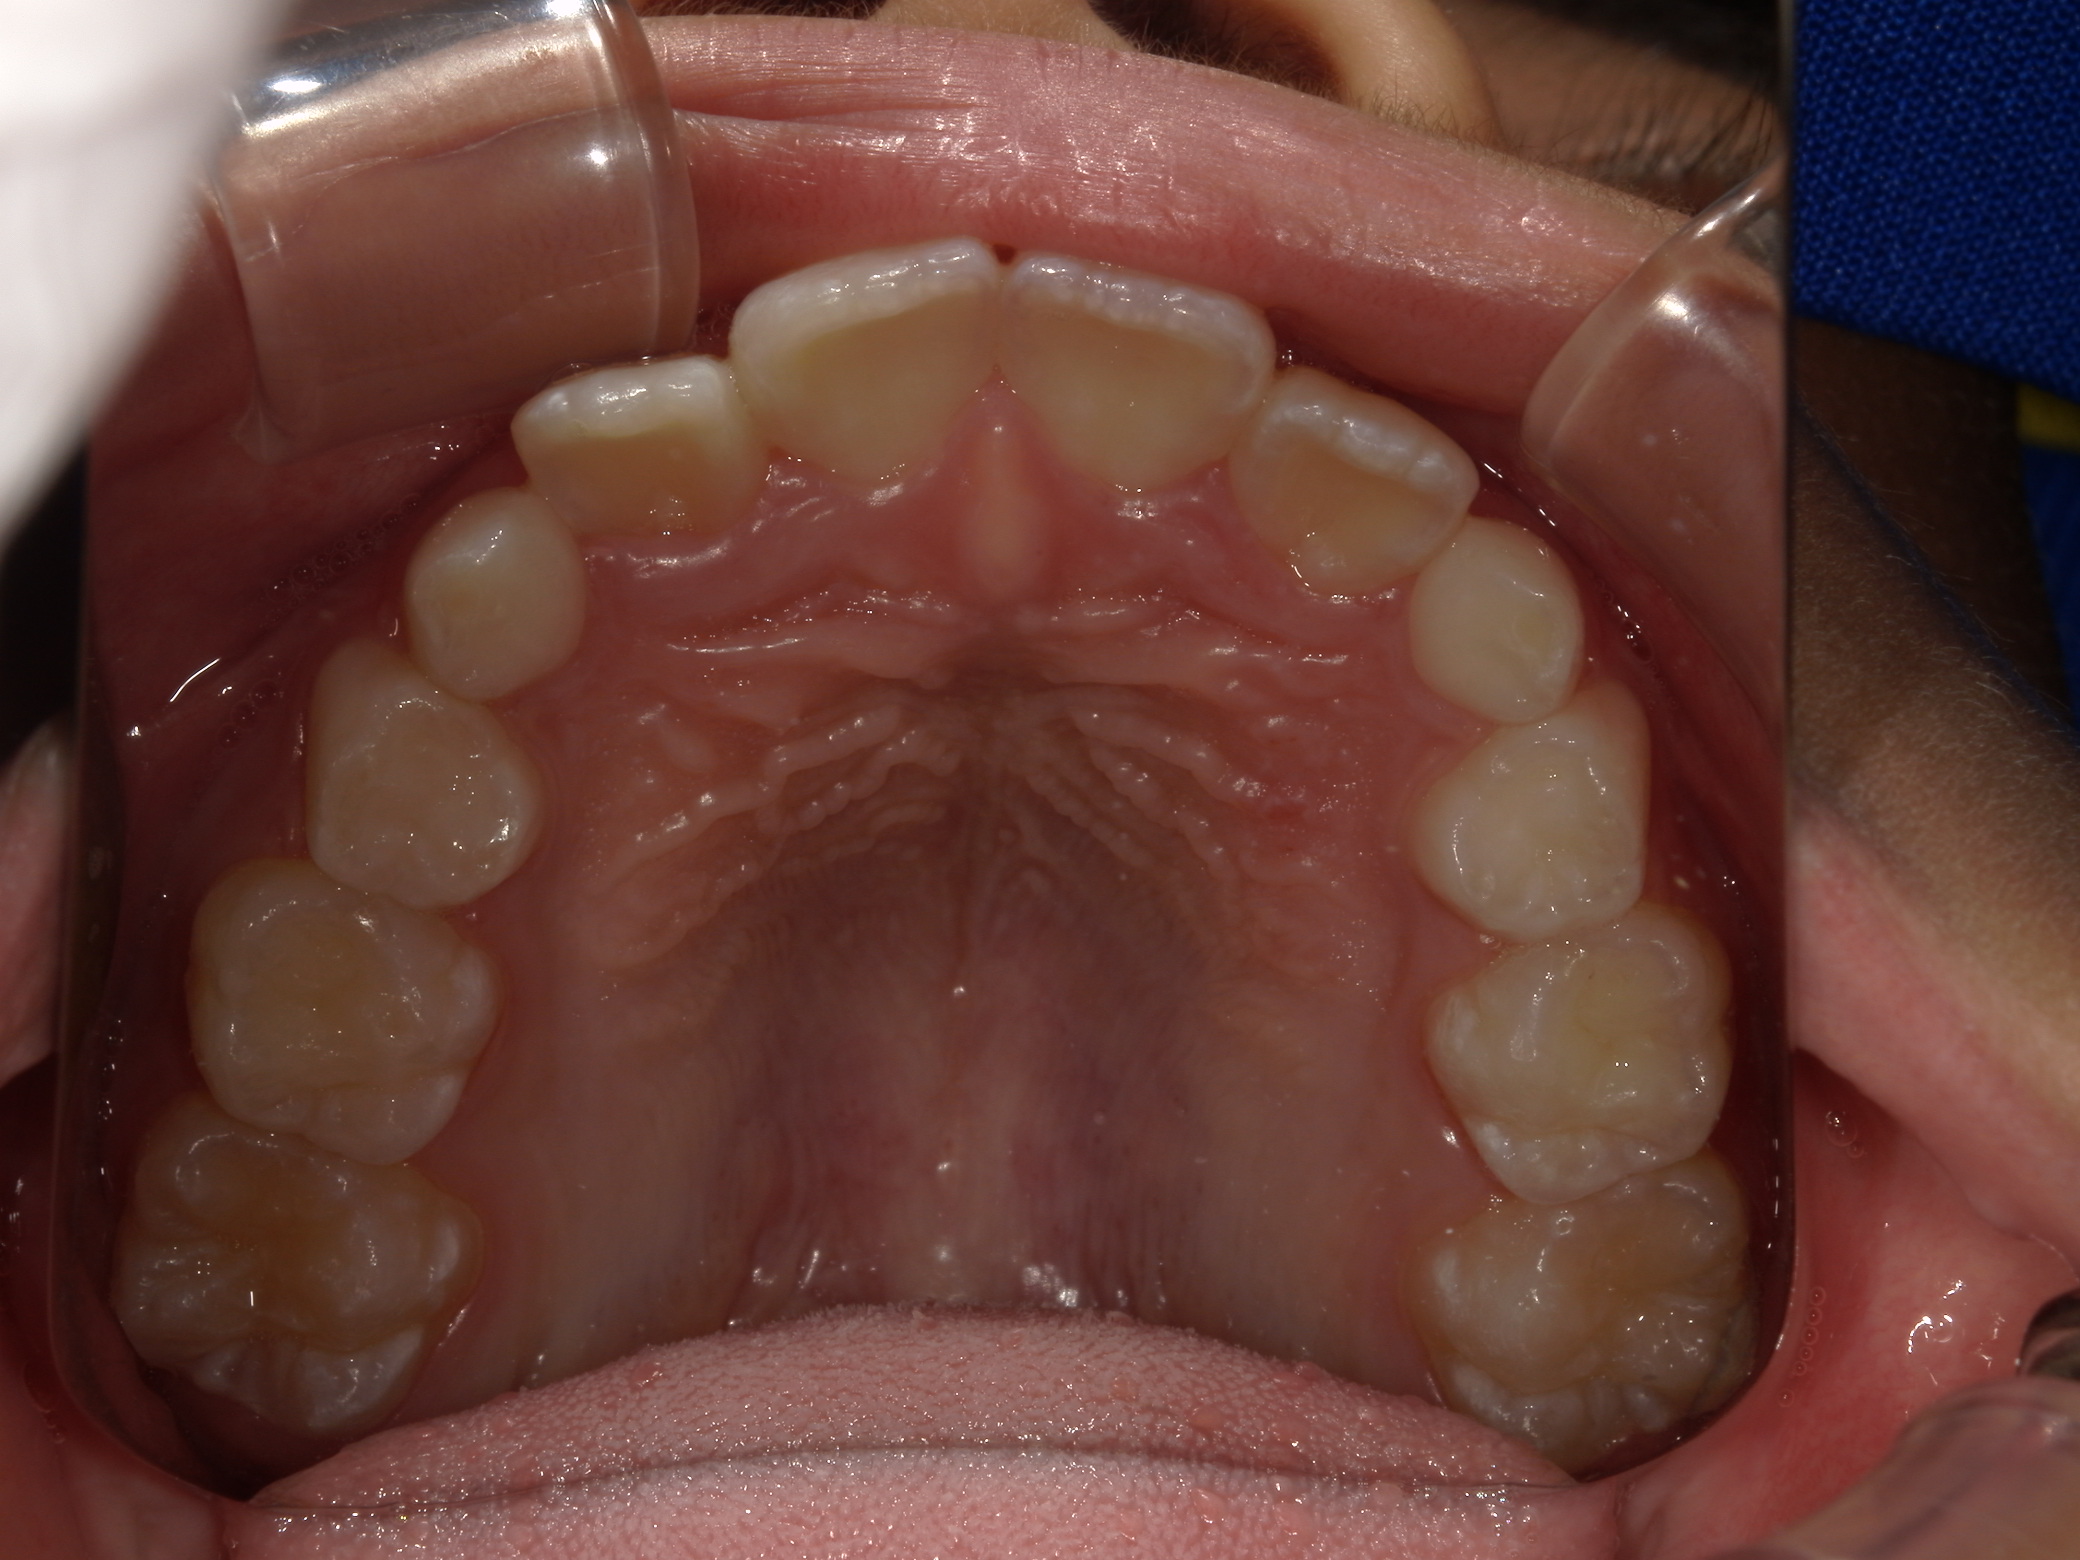

上歯前突+叢生症例 成長期

主訴 | 口元の突出感と歯並びが気になり、将来的な咬合状態を整える目的で来院された患者様です。 |

---|---|

診断結果 | 11歳1か月の女性。骨格的には日本人標準に近く、歯性の上顎前突および叢生が認められました。上下顎ともに歯列のスペース不足があり、永久歯の萌出や歯列の整列に支障をきたす可能性があると診断されました。 |

治療内容 |

|

治療後の経過 | 動的治療終了後は、上下顎の歯列が整い、口元の突出感と叢生が改善されました。審美的・機能的なバランスが取れた状態となり、現在は取り外し式リテーナーを使用し、保定期間に移行しています。 |

治療期間 | 動的治療期間:2年6か月 通院回数:25回 |

治療費用 | 720,000円 |